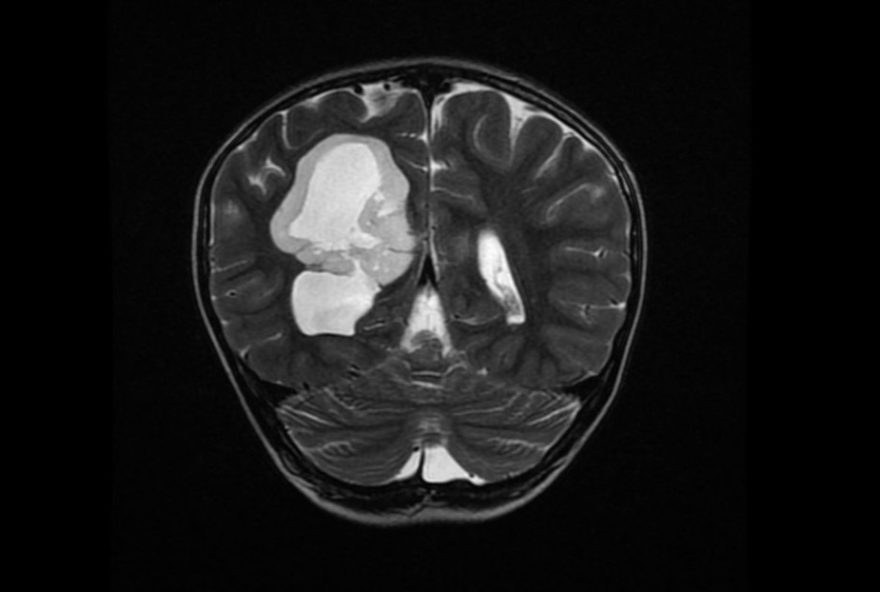

Heitor Israel, de 7 anos, passou por um grande susto no dia 1º de julho, quando foi atropelado a caminho da padaria em Pitangui. O que parecia ser apenas um acidente revelou algo muito mais sério: os médicos descobriram um tumor no cérebro durante os exames hospitalares. Após uma cirurgia delicada e meses de tratamento intenso, Heitor está em fase de recuperação, e sua mãe não hesita em chamar o processo de um verdadeiro milagre.

O acidente que mudou o destino da família de Heitor ocorreu em Pitangui, cidade localizada no Centro-Oeste de Minas. Enquanto seguia para comprar pão, ele foi atingido por um carro, resultando em um cenário inesperado: a descoberta do tumor no cérebro durante os procedimentos médicos. Após três meses repletos de desafios e expectativas, Heitor celebrou um momento emocionante ao tocar o sino da vitória na Associação de Combate ao Câncer do Centro-Oeste de Minas (Accom), em Divinópolis.